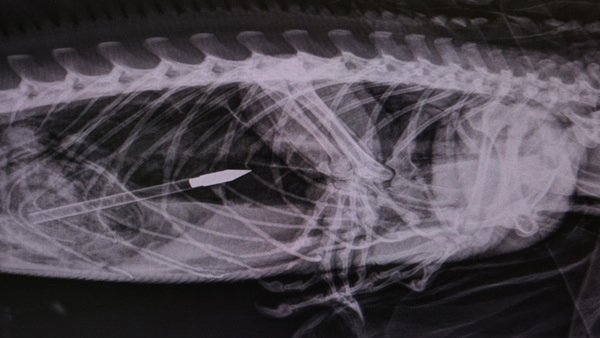

An iguana was rescued Wednesday morning in Plantation after being found with five darts or bolts sticking out of its body, from what was presumed to be a crossbow.

"We go out to this iguana thinking we could probably pull the needles or darts out of it," he said. "It's not needles or darts. It's got five crossbow arrows in it. Somebody shot it up with a crossbow."

The iguana was given pain medication and scheduled to undergo surgery that afternoon at the wildlife center, where the iguana's large size led the staff to nickname him "Godzilla."

"His prognosis right now is hard to determine because we need to see the damage internally," said Dr. Amanda Grant, a veterinarian at the center. "We'll do everything we can for him.